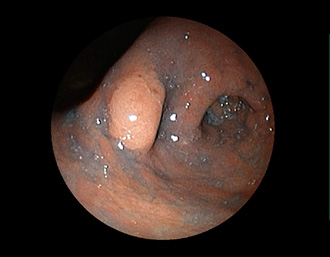

症例5:胃腺腫(84才女性)

胃角部に、大きさ10mm強のなだらかな粘膜隆起を認める。生検:Tubularadenoma with moderate atypia.Group 3。経過観察中。